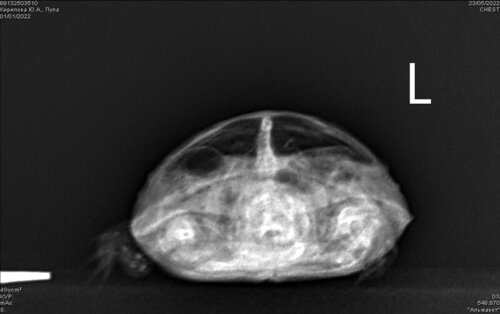

Mister.G Ваше имя: Глеб Локация: Россия, Барнаул Опубликовано: 23 мая 2022 Автор Опубликовано: 23 мая 2022 @moth

Консультанты moth Ваше имя: Мария Локация: Москва Опубликовано: 27 мая 2022 Консультанты Опубликовано: 27 мая 2022 @Mister.G если внутри какая-то стойкая инфекция, то вот так дистанционно сложно определить когда заканчивать курс антибиотика скорее всего не долечили, нужно было ещё дольше колоть лечение пока будет только для той, что делали рентген по второй точно также нужно сделать рентген сначала, прежде чем назначать антибиотики и ингаляции потому что помимо пневмонии у него ещё непонятное воздушное пространство на рентгене, и это не лёгкое и не желудок. Врач очень надеется, что просто газы в петле кишки. Также и у второго черепашонка может быть не пневмония, а те же газы, которые влияют на аппетит и активность.